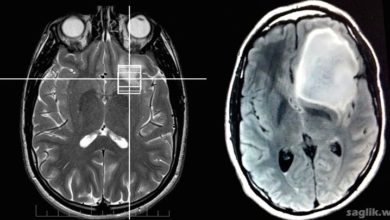

Ependimom Nedir? Ependimom Belirtileri, Nedenleri, Tedavisi

Ependimom (ependymoma), beyin veya omurilikte oluşabilen nadir bir malign tümör türüdür. Ependimoma, glioma adı verilen bir tümör grubuna aittir. Gliomalar,…